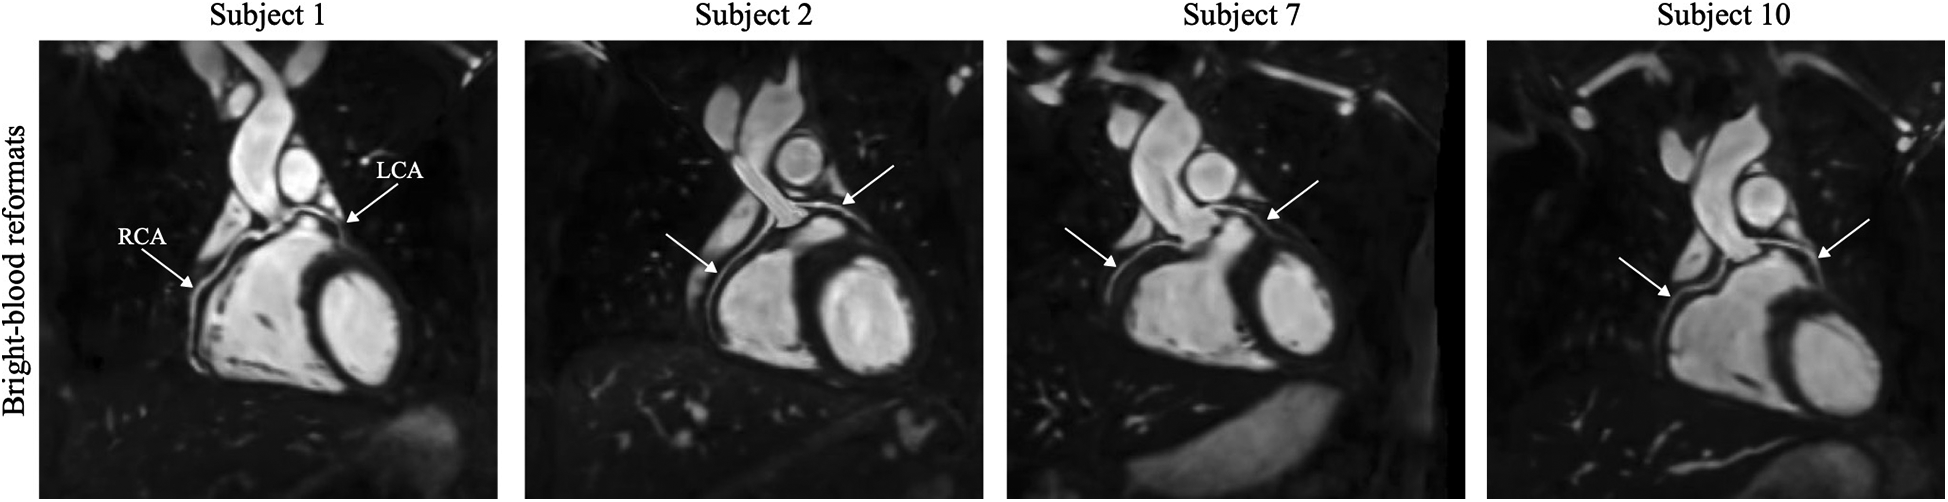

All experiments were successfully completed in healthy subjects with an average acquisition time of min. One participant was excluded from statistical analysis due to highly variable HR and significant movement during scanning. Figure 4 illustrates reformatted bright-blood datasets to demonstrate the visibility of the left (LCA) and right (RCA) coronary arteries. Isotropic resolution of 1.5 mm allowed good depiction of the coronary arteries, including distal segments and major branches. The mean vessel sharpness of was obtained and the median image quality score was 3 (good: coronary artery adequately visualized and image of diagnostic quality). In Figure 5, 3D cardiovascular anatomy is displayed via bright- and black-blood imaging for two volunteers in coronal, VAx and HAx orientations along with maps. Excellent delineation of cardiac and vascular structures was observed together with spatially uniform mapping in the myocardium. Figure 6 displays SAx views from apex to base for a representative subject alongside with corresponding bull’s-eye-plots (30 slices), showing mean and SD values as well as CoV of the LV myocardium. In Figure 7A, bright- and black-blood images and corresponding maps are shown for four representative subjects in mid-ventricular SAx slice. Comparable values were measured in the septal segments across all volunteers . Averaged values from all 3D datasets are displayed with violin plots: (apex), (mid-cavity), and ms (basal) regions (see Figure 7B). The averaged values from all segments were ms, which is consistent with literature value (13) (see Figure 7C).

Figure 4

High-resolution bright-blood images are illustrated for four subjects in multiplanar reformation. The course of the left (LCA) and right (RCA) coronary arteries is indicated by white arrows.